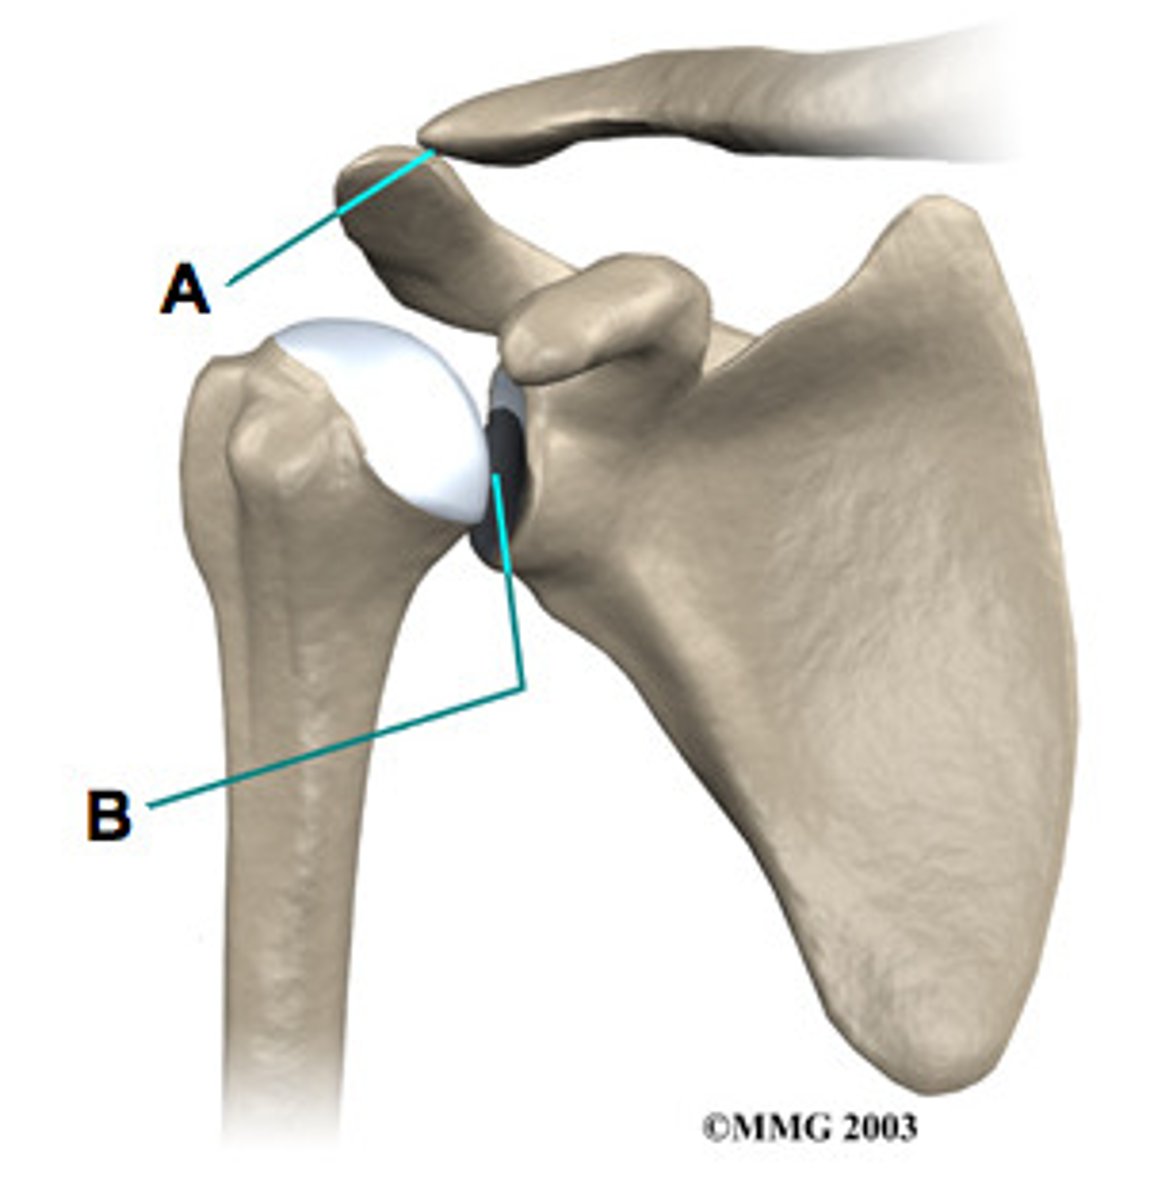

acromioclavicular j., sliding

Whats the name of joint A? and what type of joint is it?

glenohumeral j. , Ball & socket

What is B? and what type of joint is it?